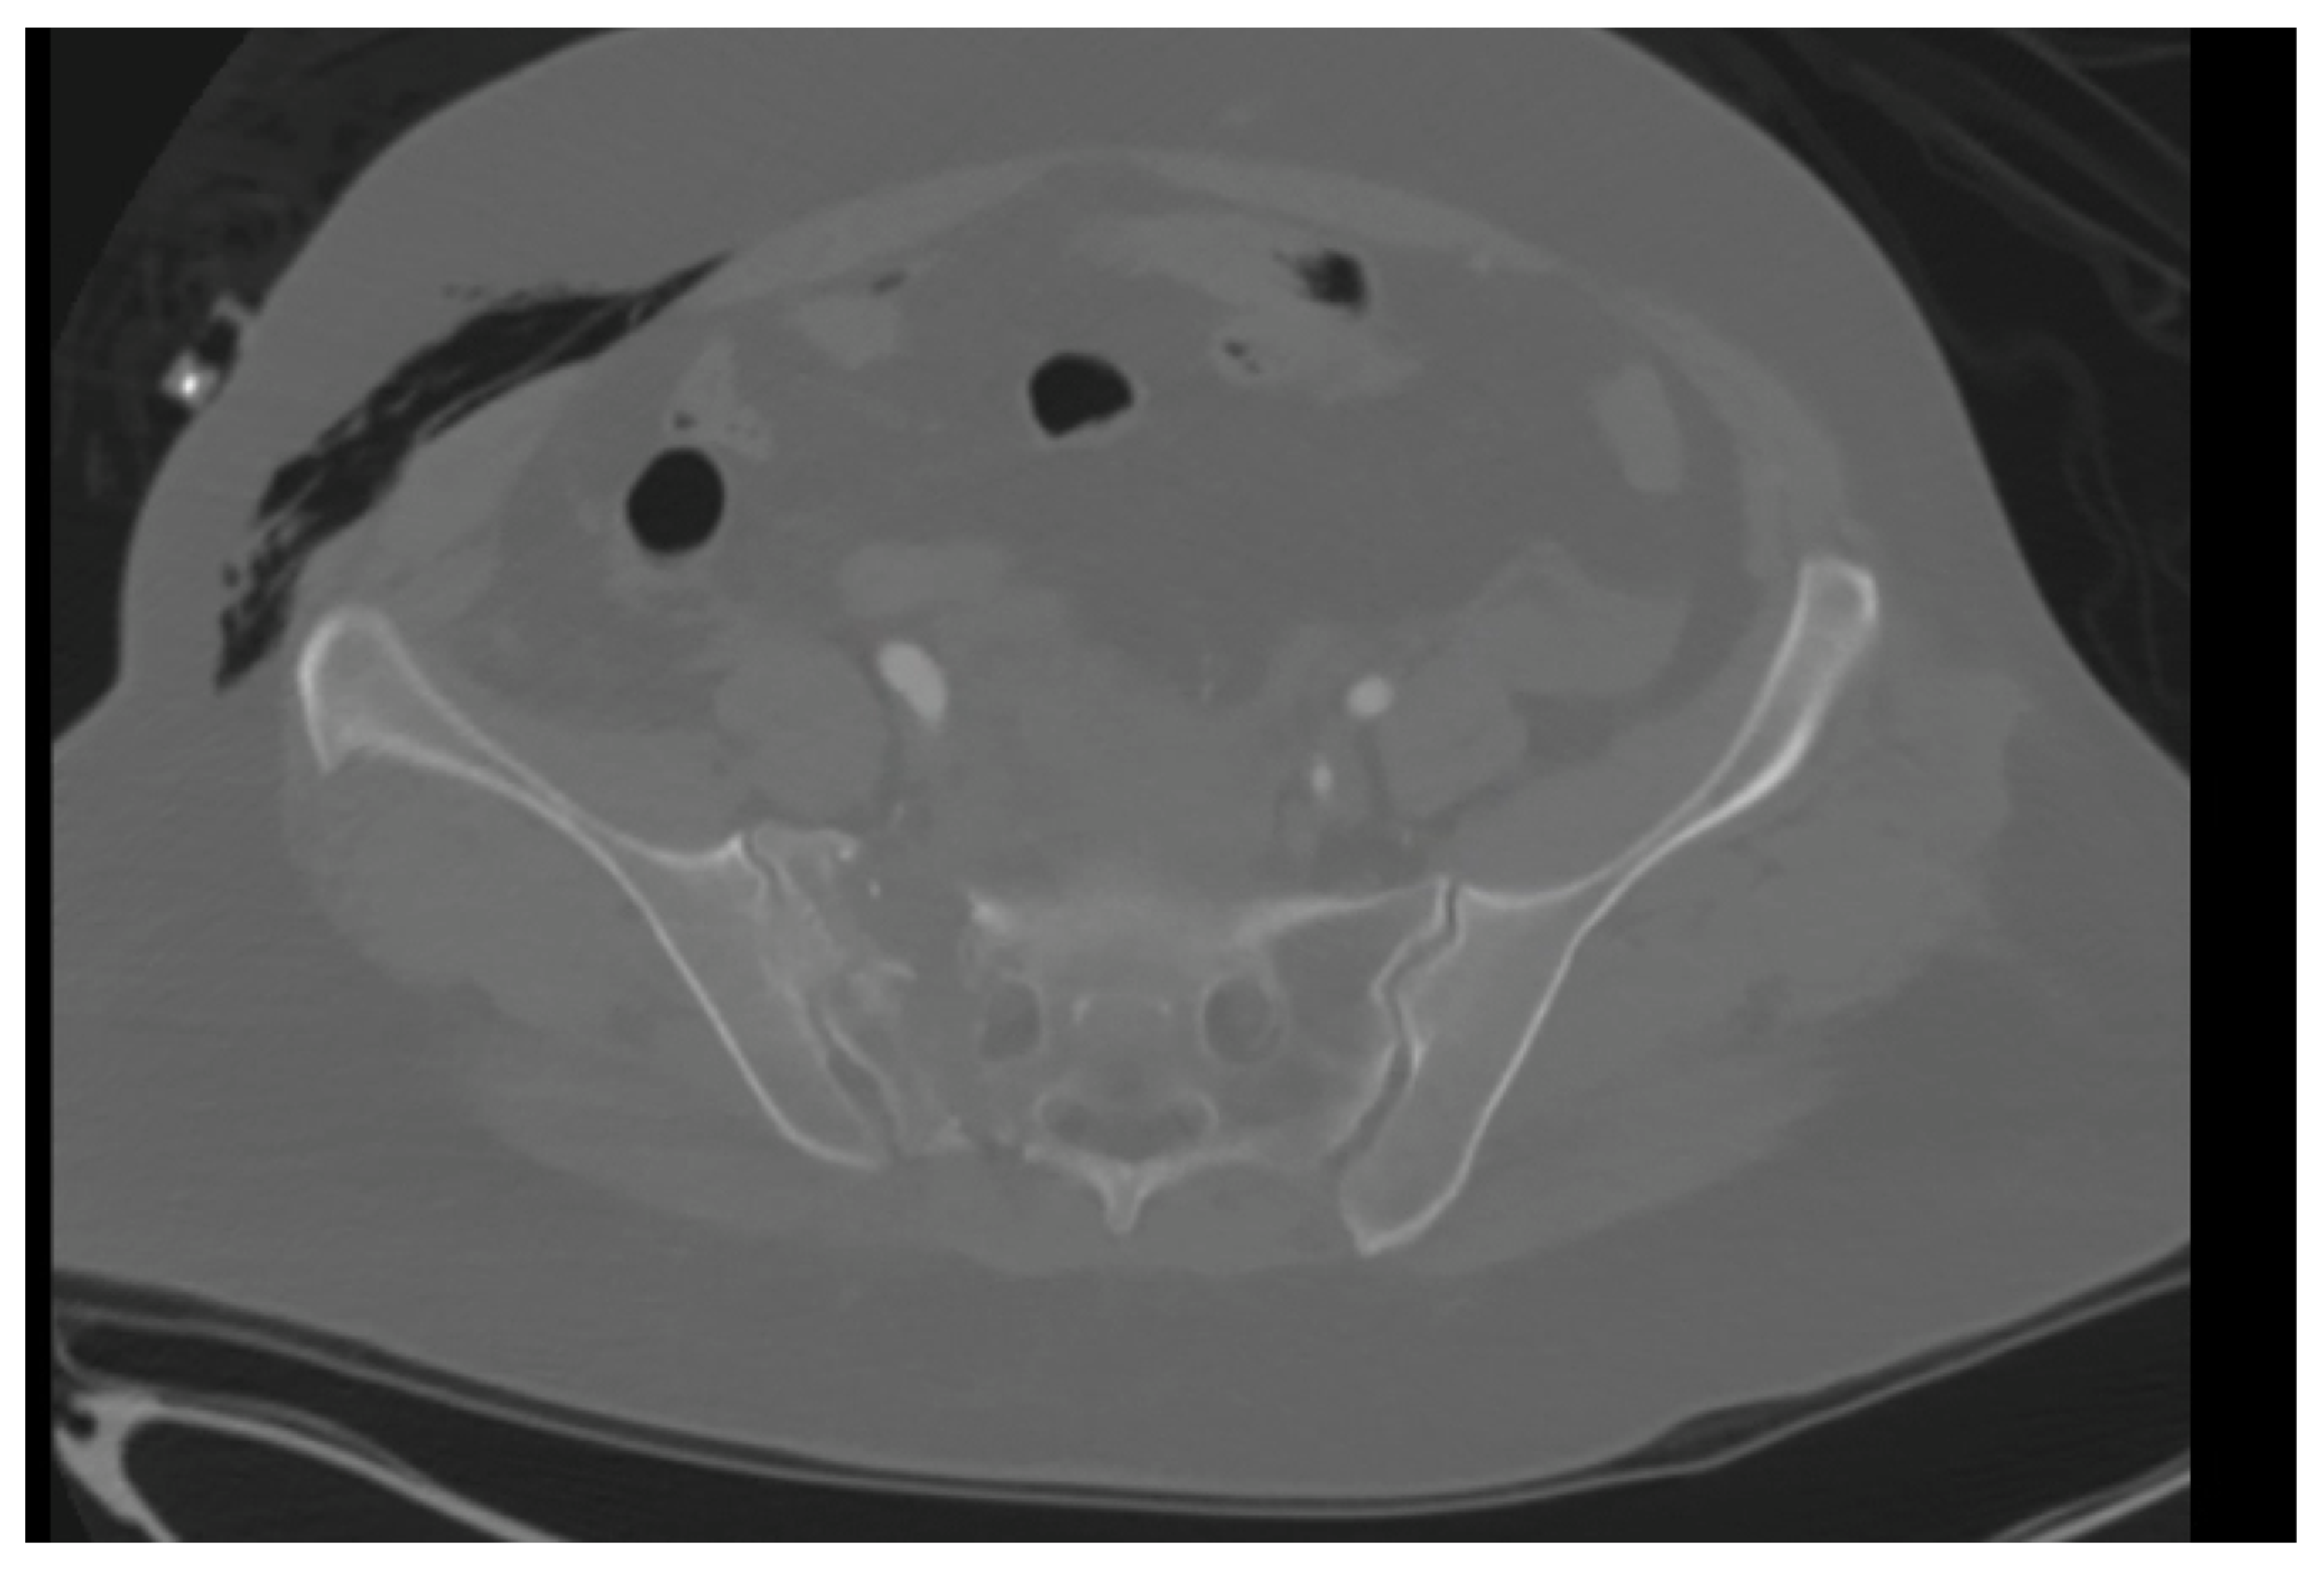

A 59-year-old female with no known past medical history presented to our level 1 trauma center, having been involved in a rollover motor vehicle collision. Plain radiographs and CT imaging demonstrated various orthopedic injuries including a Dennis type 1 vertical shear sacral fracture, bilateral superior and inferior pubic rami fractures (Figure 1 and Figure 2), right T5–T6, L1–L5, and left L2–L3 transverse process fractures, spinous process fractures of T7 and T9, and right posterior rib 4–7 fractures. Additional, non-orthopedic injuries included pneumothorax, retroperitoneal hematoma, grade 4 hepatic injury, grade 3 splenic injury, and grade 2 kidney injury. On day 3 of presentation, the patient was stable enough for operative fixation from the orthopedic surgery team.

Figure 2. A still image from an axial CT of the pelvis in a skeletally mature individual better demonstrating a vertical shear sacral fracture.